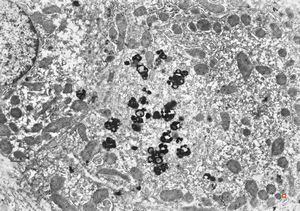

M,58y. | crystalline inclusions in hepatocyte after unknown medication